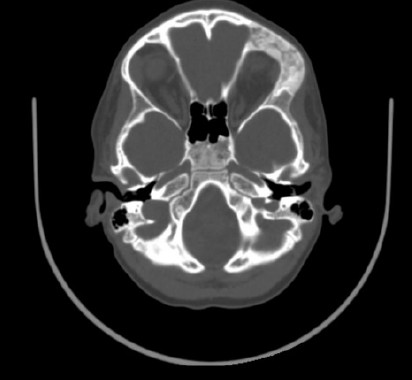

The MSCT imaging revealed edema, deformity structure exhibits uneven compaction resembling a “ground glass” appearance in the right frontal bone (Figure 5). A diagnosis of fibrous dysplasia of the right frontal bone was established.

Additionally, a preoperative three-dimensional image and axial computed tomographic scan illustrate the distinctive ground-glass opacification characteristic of fibrous dysplasia affecting the left frontal, temporal, and sphenoid bones.

Fig. 5. A preoperative coronal computed tomographic image obtained on September 2023, reveals dysplastic growth of the left temporal bone, which is associated with frontal involvement and displacement of the orbital contents